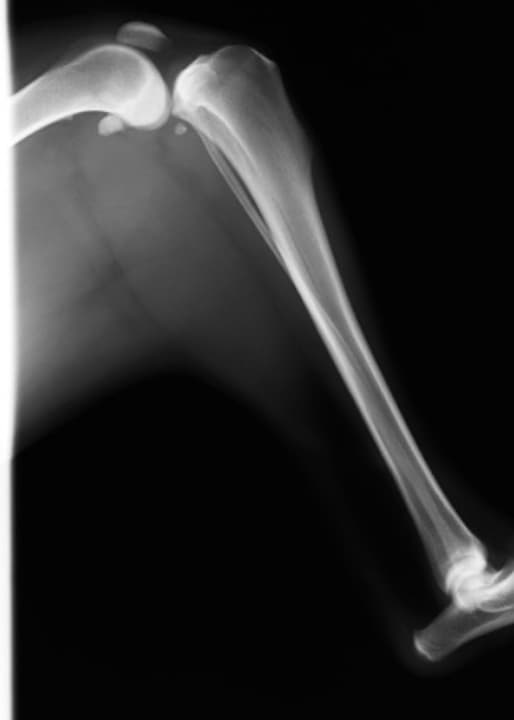

前十字靭帯とは、膝の動きをコントロールする靱帯が断裂した状態です。前十字靭帯が断裂すると、膝関節が不安定になり、体重をのせて歩行が困難になります。小型犬では膝蓋骨脱臼も併発してることが多いです。

症状は後足の挙上です。患肢が完全に地面につかず、一般的に痛みを伴うので、足を触ると怒ったりします。

一般的にレントゲンや触診での診断が多いですが、レントゲンで靭帯を確認することはできません。

当院はMRIがあるので、靭帯の断裂をMRIによって診断することが可能です。 -